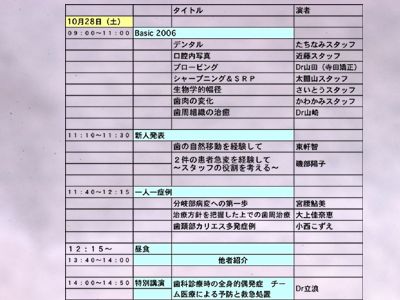

スタッフミーティングに臨む前に参加者にひとつの症例を提示し、その予後を予測してもらいました。

症例:’93初診時、右下45遠心に垂直性骨欠損がありプロービングデプス>8〜9mmでした。(当時の)新人DH Kによる非外科的ルートプレーニングにてPD2〜3mmに減少し、歯槽骨頂線が明瞭になりました。当時はそれを骨吸収の停止すなわち安定と考え一応のゴールの目安としていました。でも「その後」はみてはいませんでした。

「それから13年後の2006年、この骨はどのように変化したでしょう?」というのが宿題です。

それを頭のすみに残しながら各医院が垂直性骨欠損への対応としての症例を提示しました。また骨欠損とレントゲンの注意事項を川上先生斉藤先生が模型実験で示してくれました。

さて宿題の症例にもどって、13年後の解答です。

レントゲン上でもリエントリーでの肉眼所見でも骨欠損は認められませんし、ふたつの実験結果からの反証とも異なると思います。

今回の症例では咬合調整は一切行っていません。ルートプレーニングのみによる大きな治癒の可能性を再確認しました。プロービングデプス、デンタル上での骨欠損とその変化、歯周病の治癒の様式etc.いくつものテーマが示唆されると思います。いずれも「剱Basic」として繰り返し学んでいることです。

垂直性骨欠損には咬合性外傷を伴うものがおおいため、咬合調整をして自然移動をはかり骨レベルを揃えるという手法がとられる事が多いですが、非可逆的処置である削合とくに抜髄を伴うときなどは、そのリスクベネフィットバランスをよく天秤にかける必要があることは当然です。